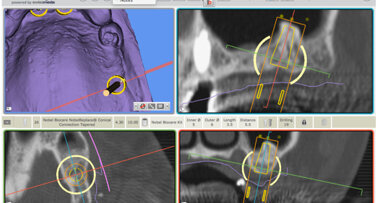

3. La place de plus en plus grande prise par le numérique depuis l’élaboration des plans de traitement, l’analyse du risque, la mise en place des implants et la réalisation rapide de pièces prothétiques grâce à la CFAO.

Si je dois équiper un maxillaire et/ou une mandibule atrophique, rien ne doit manquer à l’appel, sous peine de ruiner les différentes étapes et de faire capoter l’opération, voire de mutiler le patient. Dans ce cas, il est impératif d’utiliser tout ce que la technologie moderne nous apporte depuis la simulation numérique, les guides informatiques